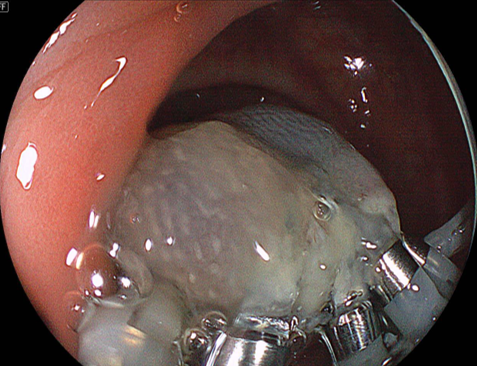

切除後の潰瘍底(かいようてい):術直後の出血なく切除

されました。

切除後の潰瘍底に後出血予防のクリップを追加しました。

この症例は、術中出血および後出血を認めませんでした。